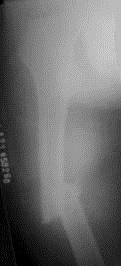

病历摘要: 患者×××,男性,34岁,车祸致伤右大腿后肿胀、疼痛、畸形,活动受限2小时。查体:右大腿肿胀,成角畸形,骨连续性中断,右足背动脉搏动存在,右足...

问题 病历摘要: 患者×××,男性,34岁,车祸致伤右大腿后肿胀、疼痛、畸形,活动受限2小时。查体:右大腿肿胀,成角畸形,骨连续性中断,右足背动脉搏动存在,右足伸屈功能正常。 该患者有可能下列哪些疾病?

选项 A、右股骨干骨肿瘤 B、右髋关节脱位 C、右股骨颈骨折 D、右股骨干病理骨折 E、右股骨髁上骨折 F、右股骨粗隆间骨折 G、右股骨干骨折

答案 DEG